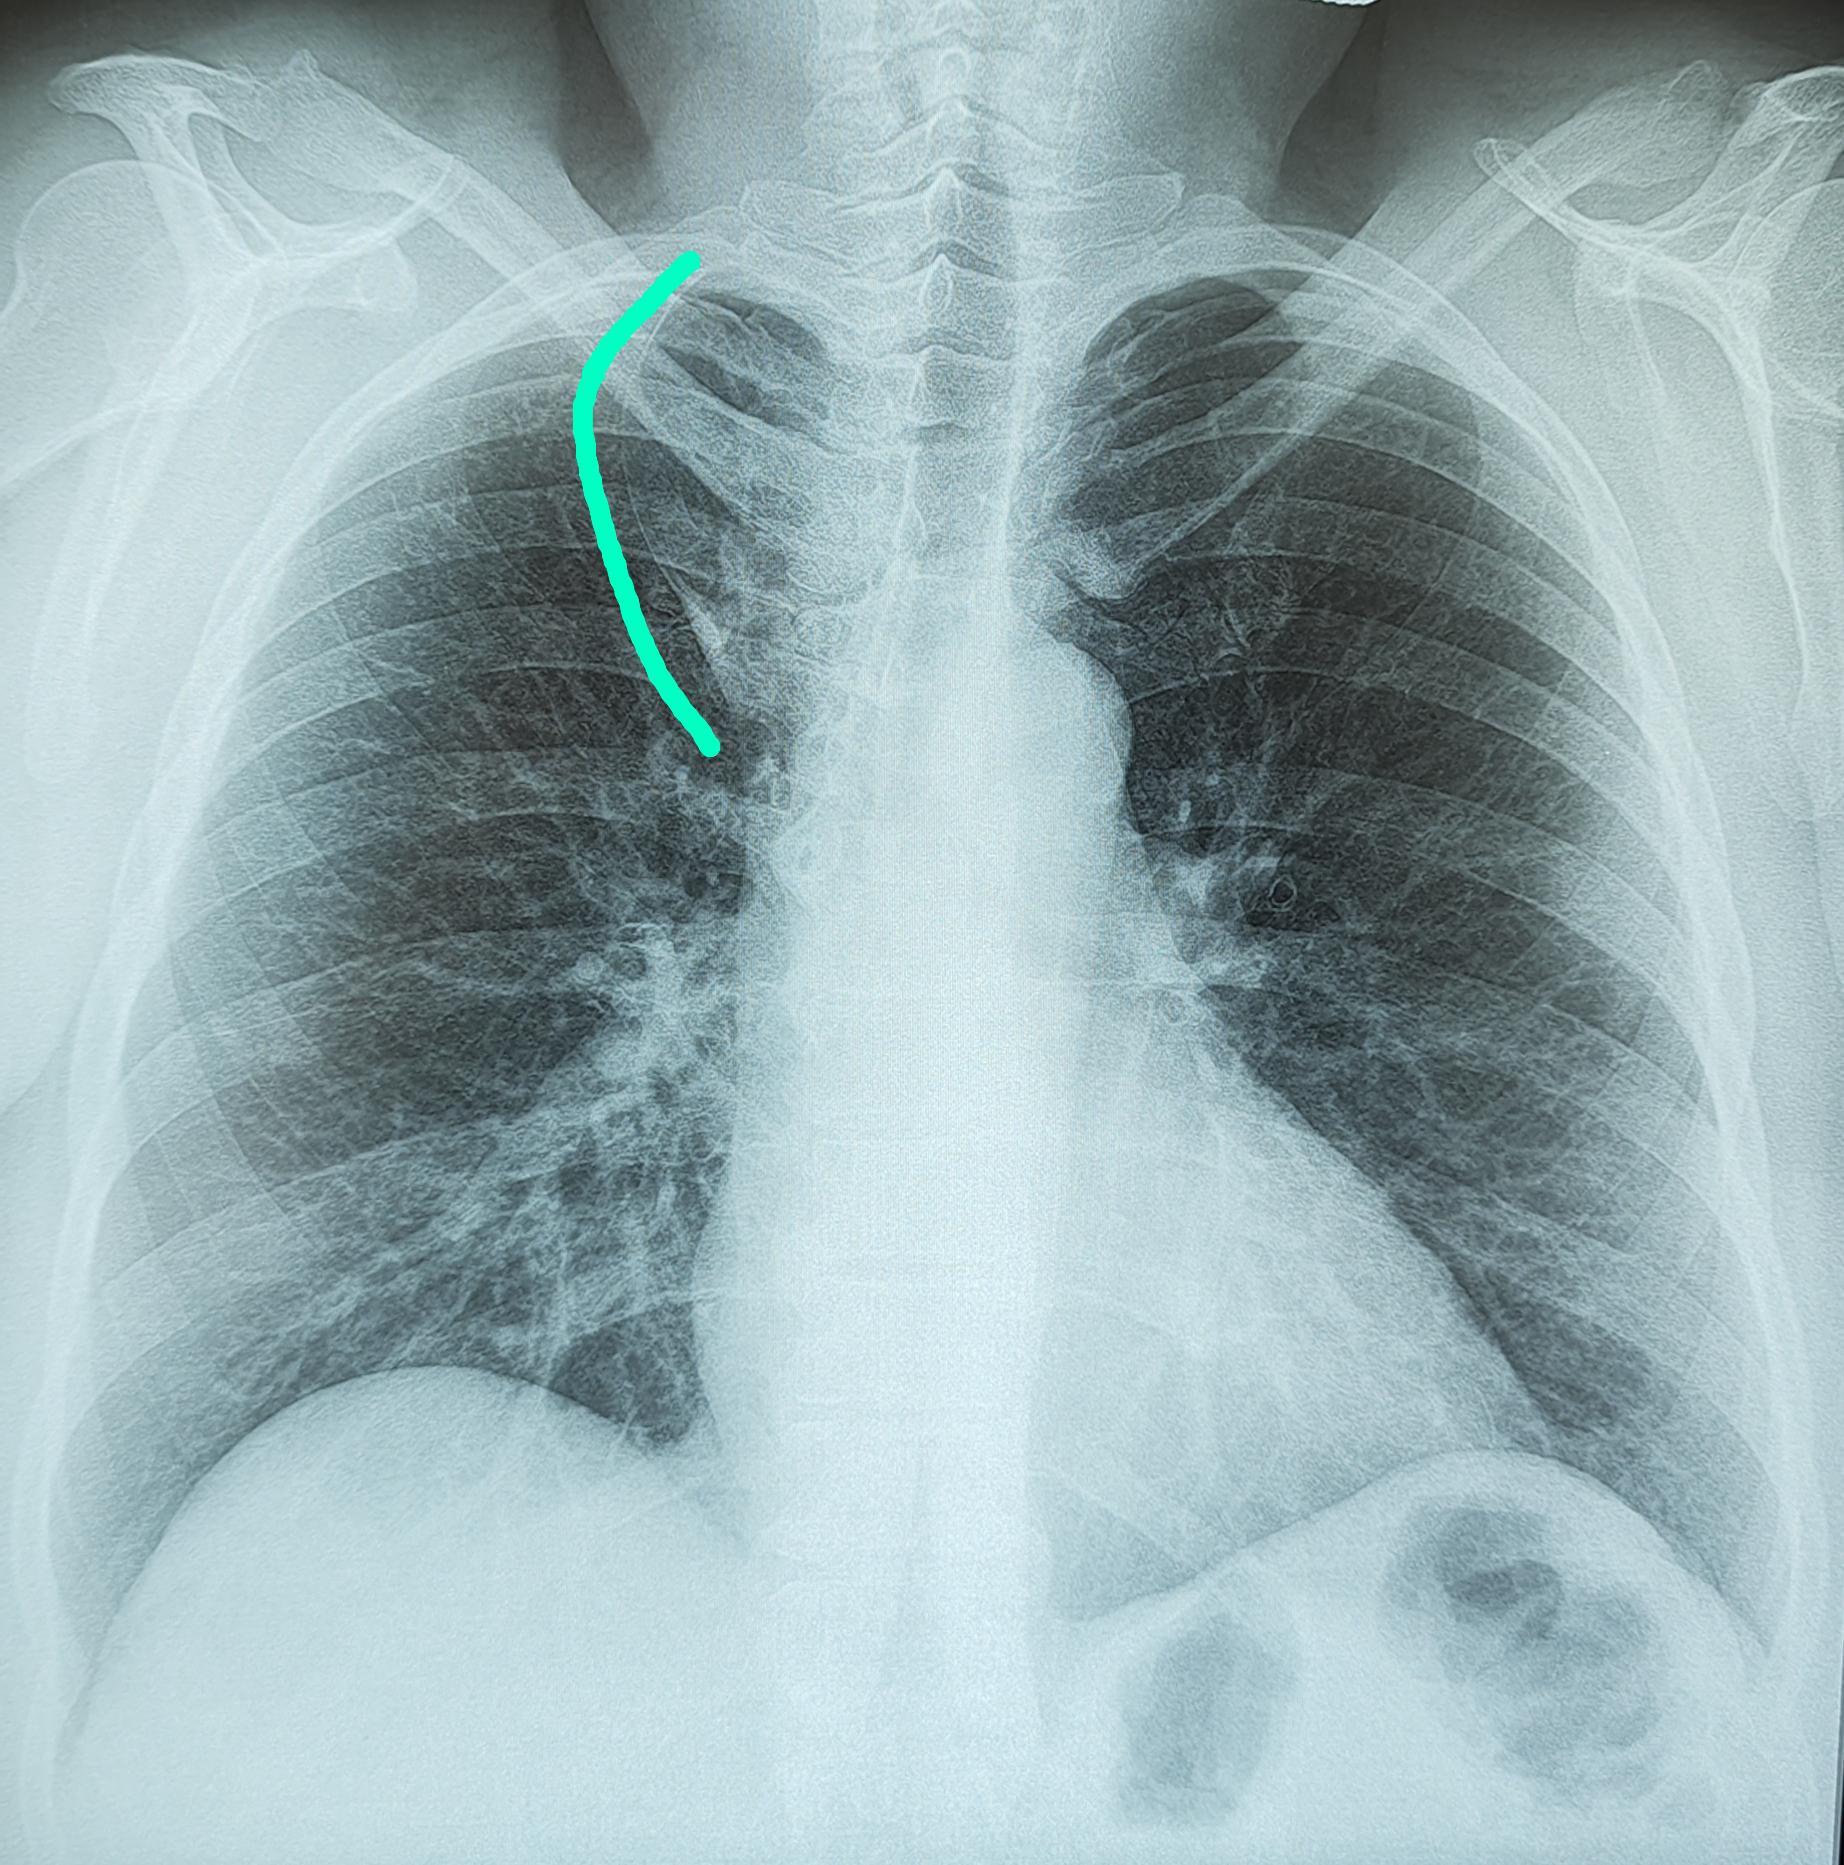

Справа по парастернальной линии, чаще на уровне 1-го межреберья (иногда на уровне хрящевой части 1 или 2-го ребер) определяется небольшая в форме вытянутой капли тень (от 0,3 до 0,8 мм ширины и от 0,6 до 2,5 мм длины) с четкими контурами. Эта «капля», заостряясь кверху, переходит в нежную (волосяную) линейную тень добавочной междолевой щели; она направлена кверху и дугообразно изгибается выпуклостью кнаружи.